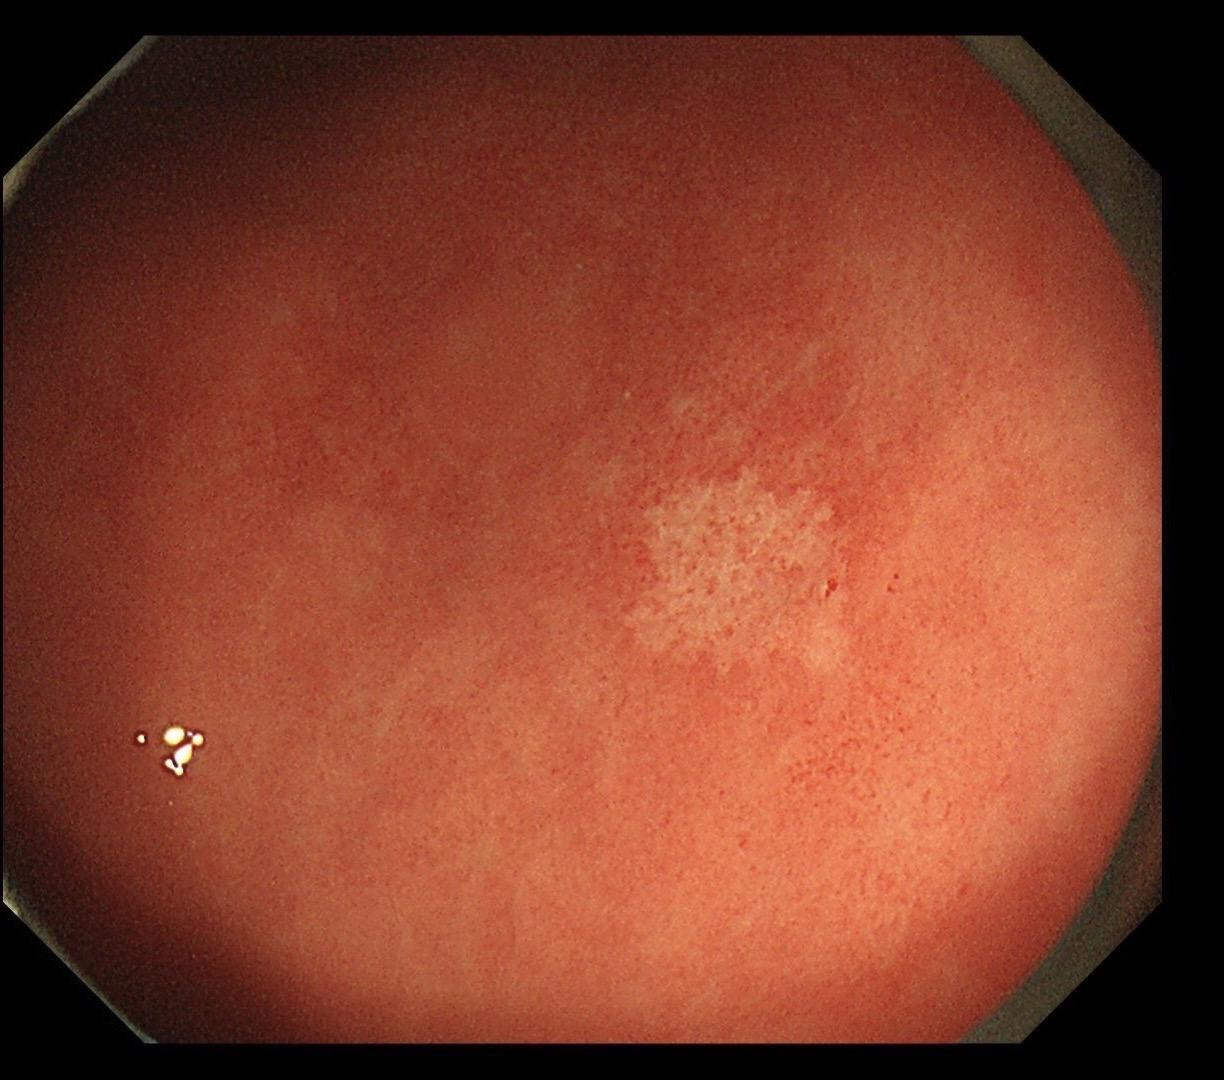

男,40岁,胃双发褪色调病变。慢性胃炎复查,3年前胃镜未见异常,Hp阳性背景,萎缩不明显,胃体下部大弯见一褪色调病变,浅凹陷,5mm左右,换用放大内镜观察,表面结构缺失,血管异型明显,未分化可能性大……胃窦后壁见一白斑,无高度差,NBI浅茶色,放大草草看了下,似有边界,IP增宽,活检待病理……小哥哥胖得几乎没脖子,腹式呼吸太明显~😖